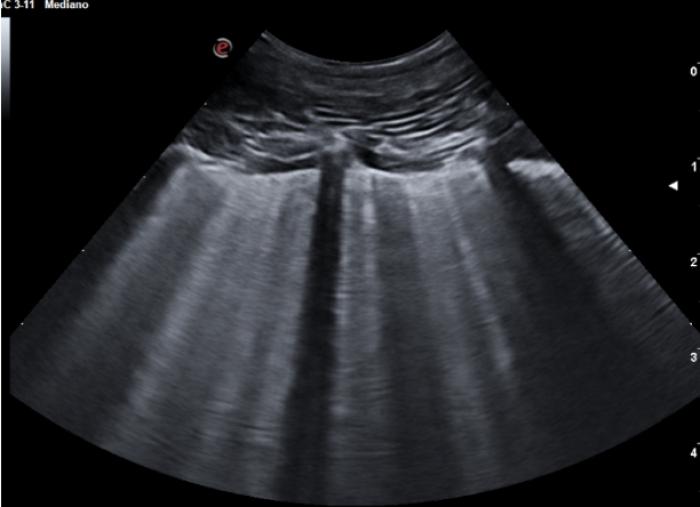

Comenzaremos posicionando el transductor perpendicular a las costillas en uno de los espacios intercostales, pudiendo evaluar al menos el espacio entre dos costillas, la línea PP y no más de 2-3 cm de profundidad de campo (Figura 1A-B).

En algunas localizaciones podemos observar una pequeña discontinuidad de la LP que corresponde a las incisuras existentes entre los diferentes lóbulos, las cuales no irán acompañadas de más signos considerados patológicos, puesto que son visibles en pacientes sanos (Figura 2) (Vídeo 1).